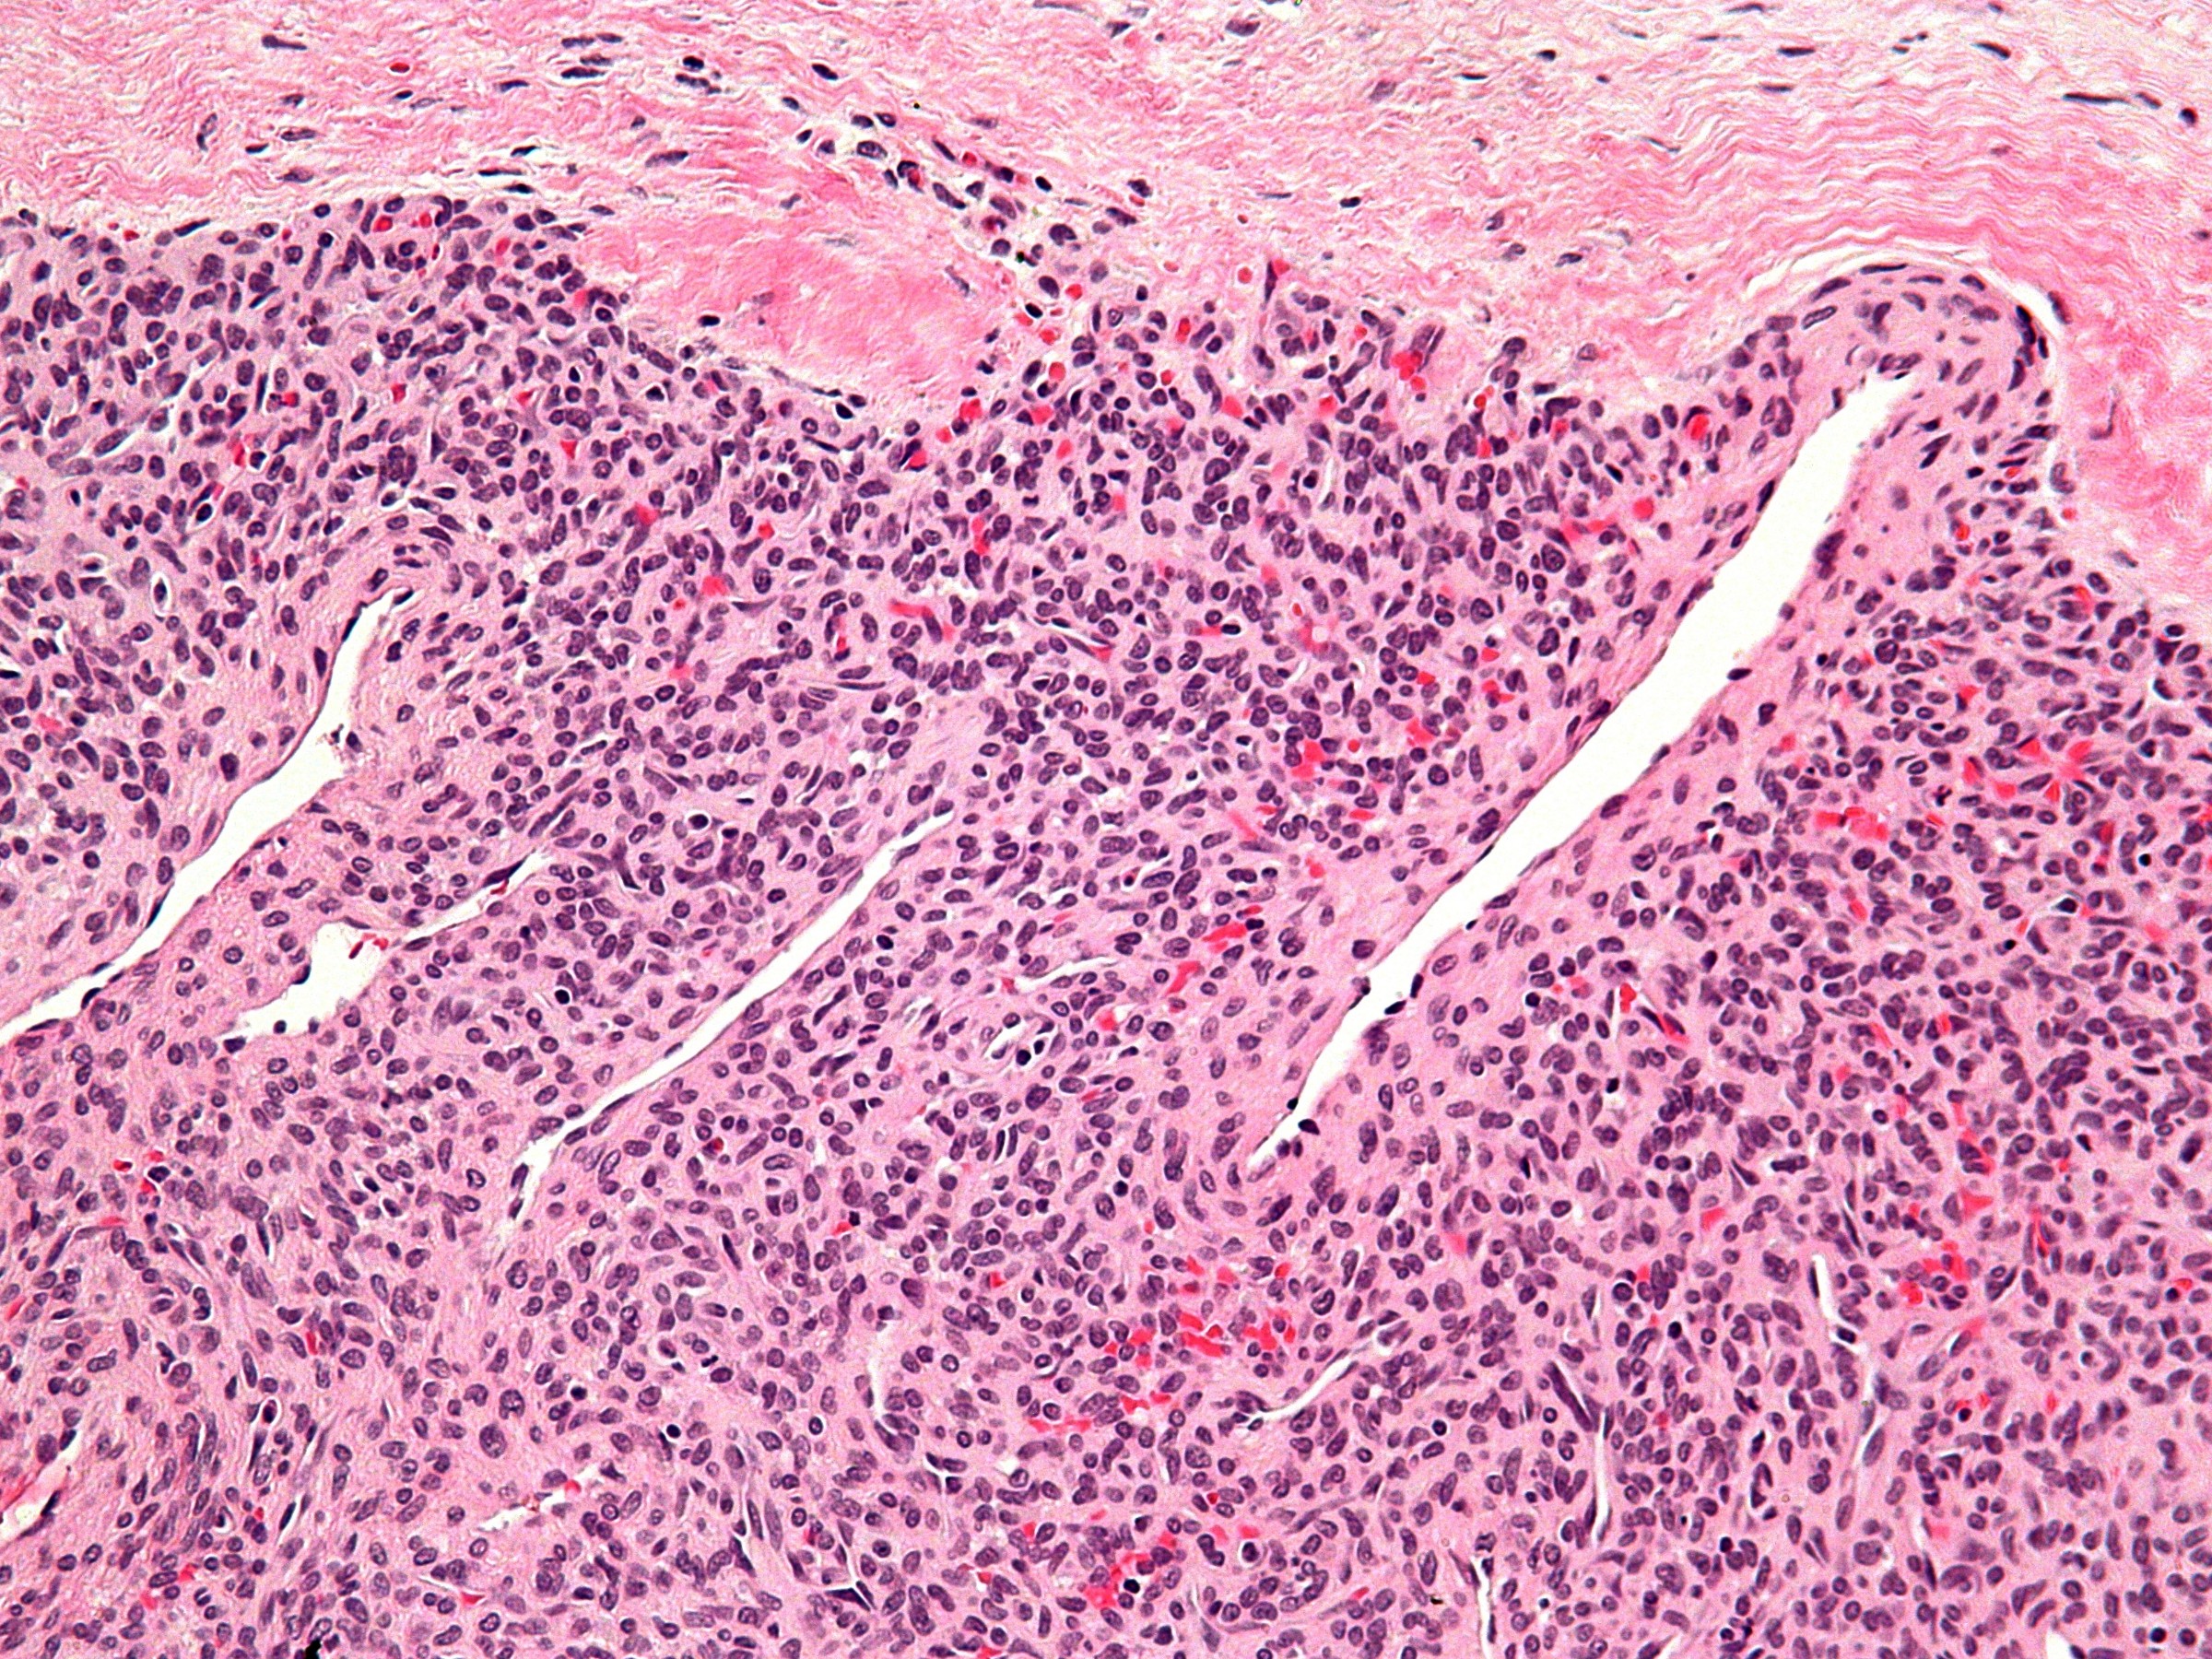

Scherp begrensde celrijke gebieden met daarin vertakkende bloedvaten, en concentrisch rond de vaten gelegen spoelvormige cellen zonder cytonucleaire atypie, weinig mitosen. De tumorcellen zijn positief voor SMA (smooth muscle antigen), myofibroblasten zijn positief voor HHF35. Soms aankleuring voor CD34 en desmine. Bij de zeldzame maligne variant werd een hoge mitoseactiviteit, centrale necrose en doorgroei in de weke delen beschreven. De histologische DD omvat angioleiomyoma, glomustumor, glomangioma en glomangiopericytoma.

PA myopericytoom PA myopericytoom